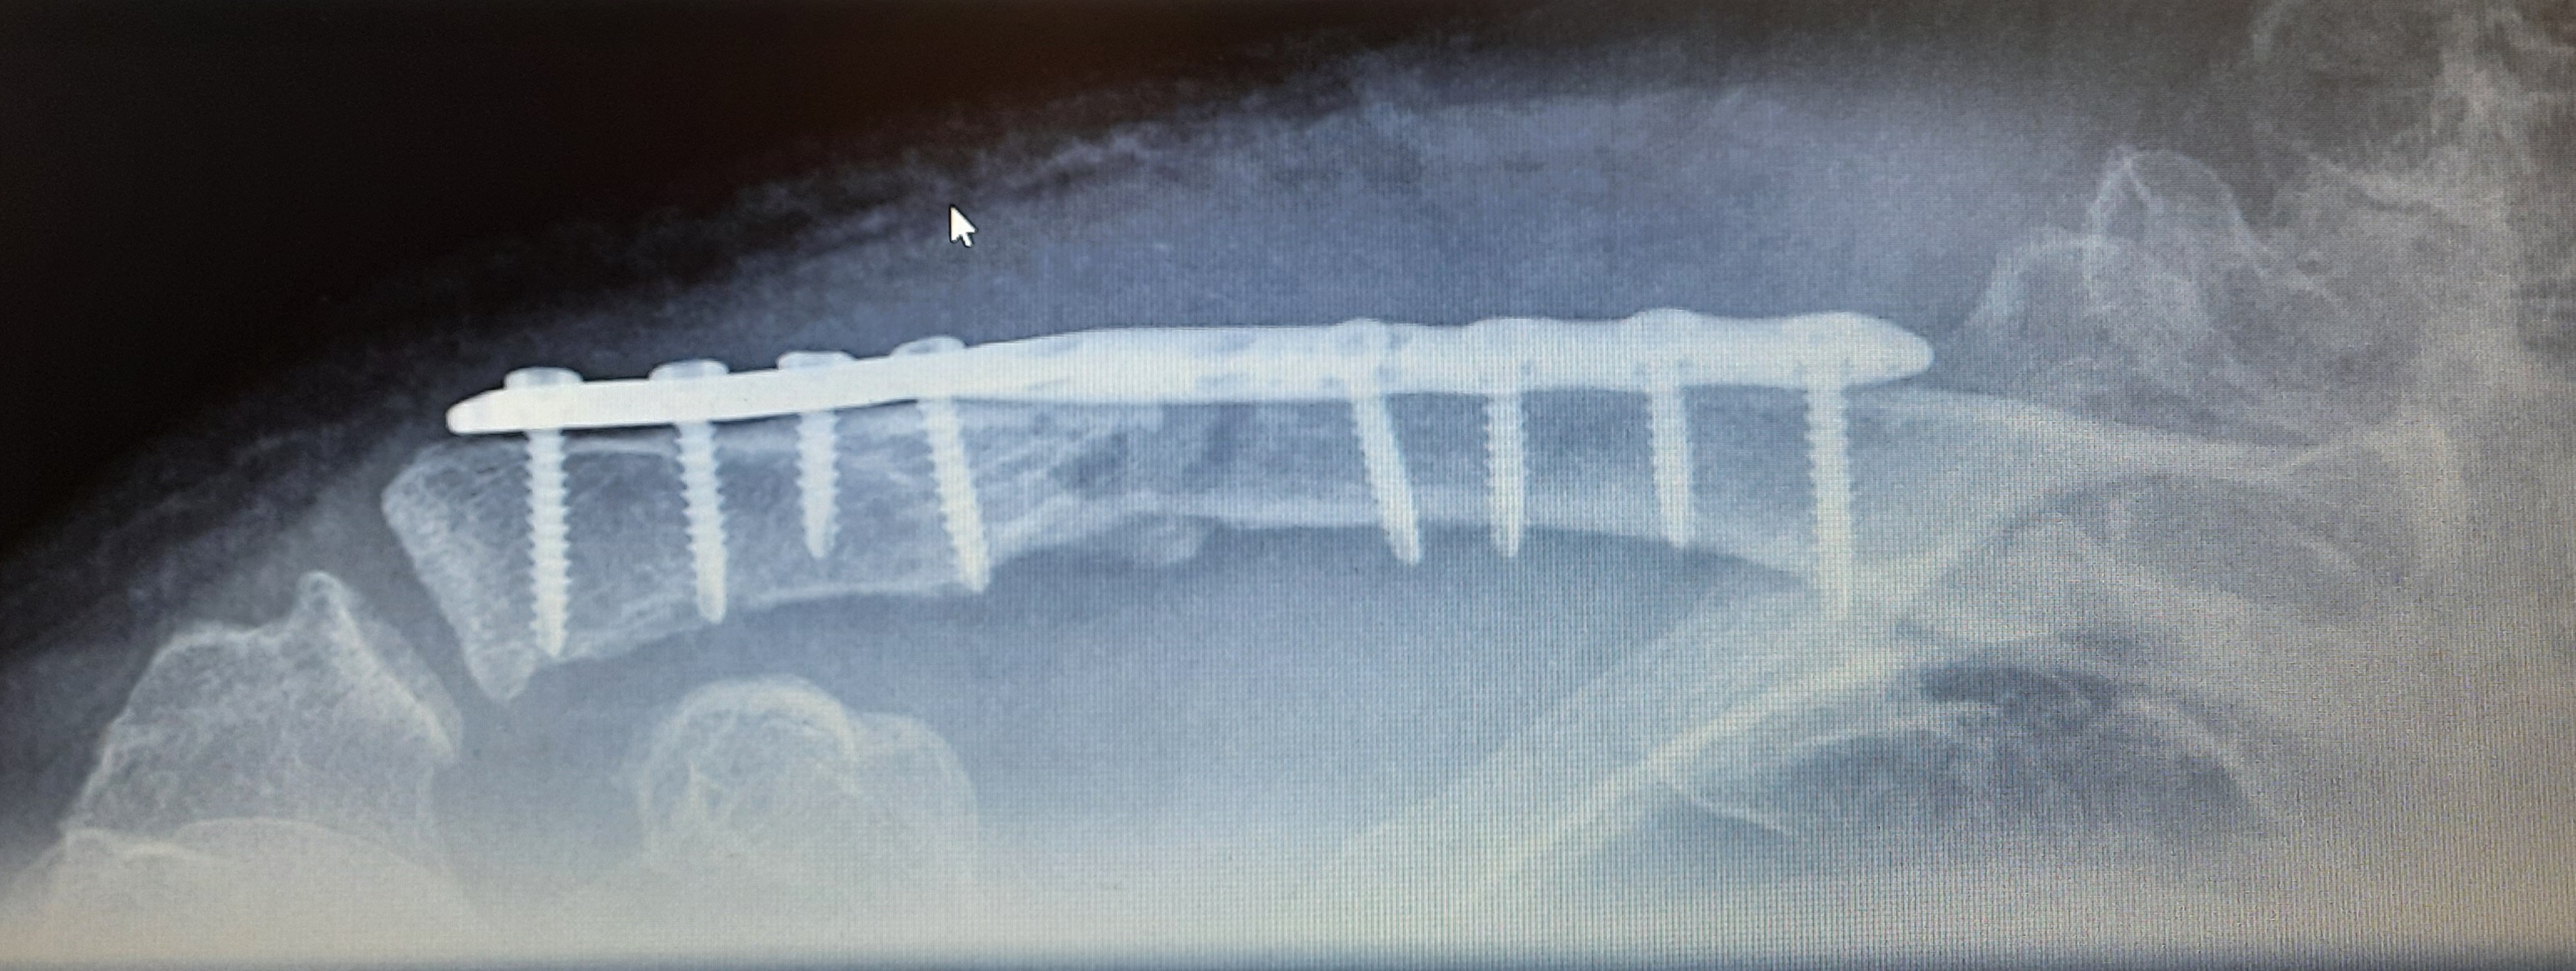

Meine wurde zwar raus genommen wie oben gesehen aber gleich ersetzt mit noch mehr Schrauben. Die erste ist ausgerissen. Hier die neue. Habe ich diese Woche Dienstag gekauft. ;-)Meine Bonebridge is noch drinAnhang anzeigen 444429